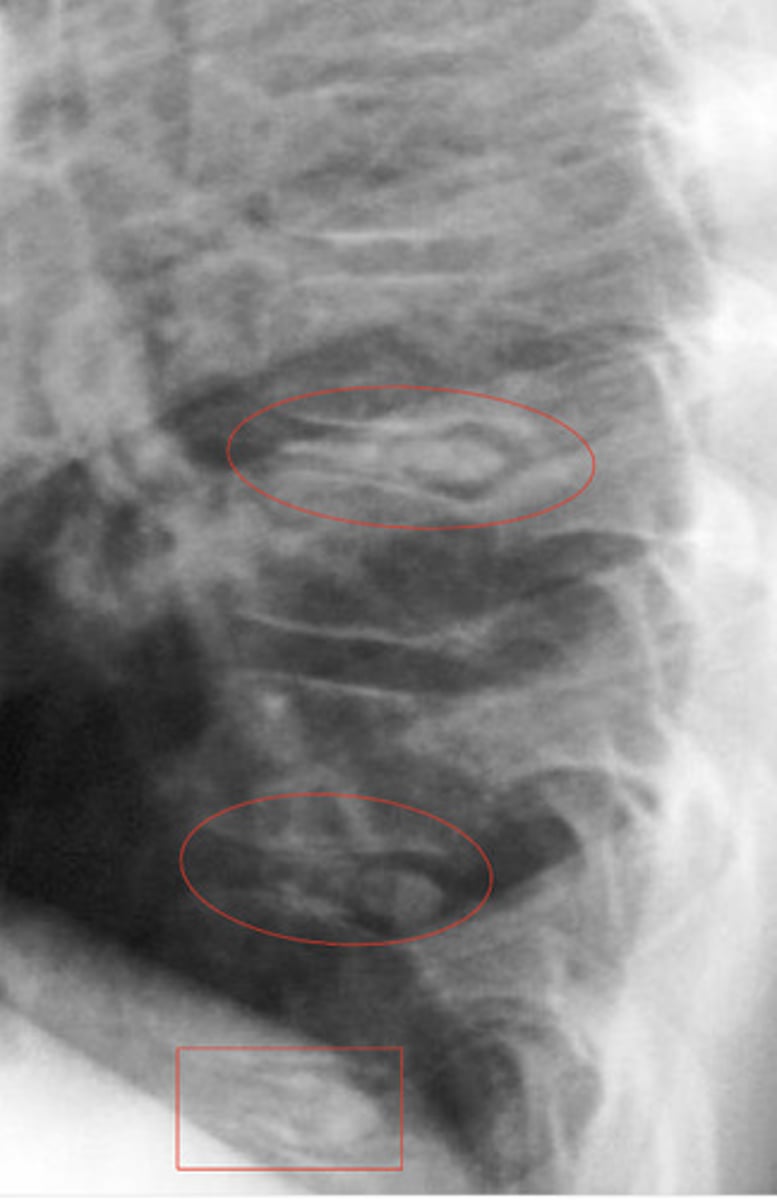

Disc calcification

What is the red

Calcification of the posterior vertebral line

Looks like fracture, not actually

What is the blue?

What is the red?

DISH (mid body to mid body)

What is in the red?